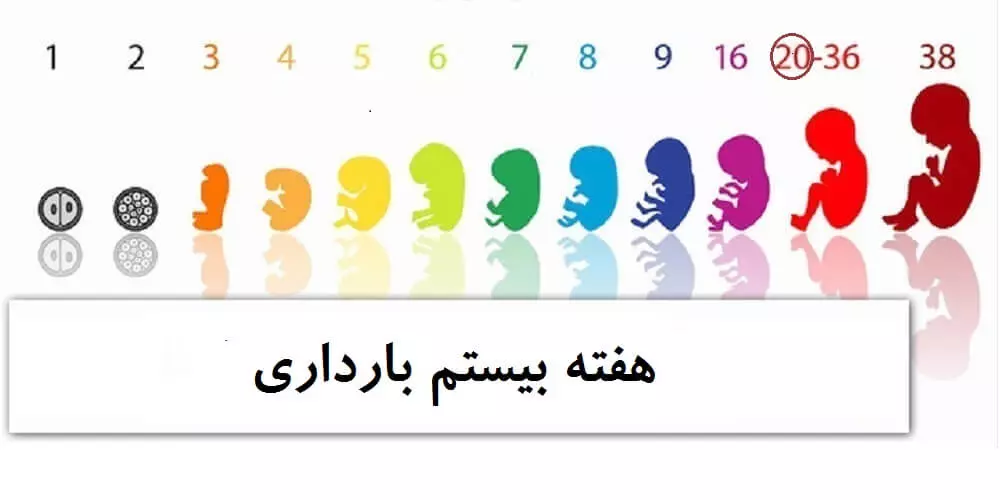

وضعیت مادر و جنین در هفته بیستم بارداری

وضعیت جنین در هفته بیستم بارداری

وزن جنین ۲۰ هفته ای تقریبا ۳۱۰ گرم و قد او ۱۶ تا ۱۸ سانتی متر می باشد. بدن کودک کاملا با موهای کرک دار لانوگو پوشیده شده است. لانوگو مایع ورنیکس را ترشح می کند تا از پوست جنین در برابر مایع آمنیوتیک محافظت کند.